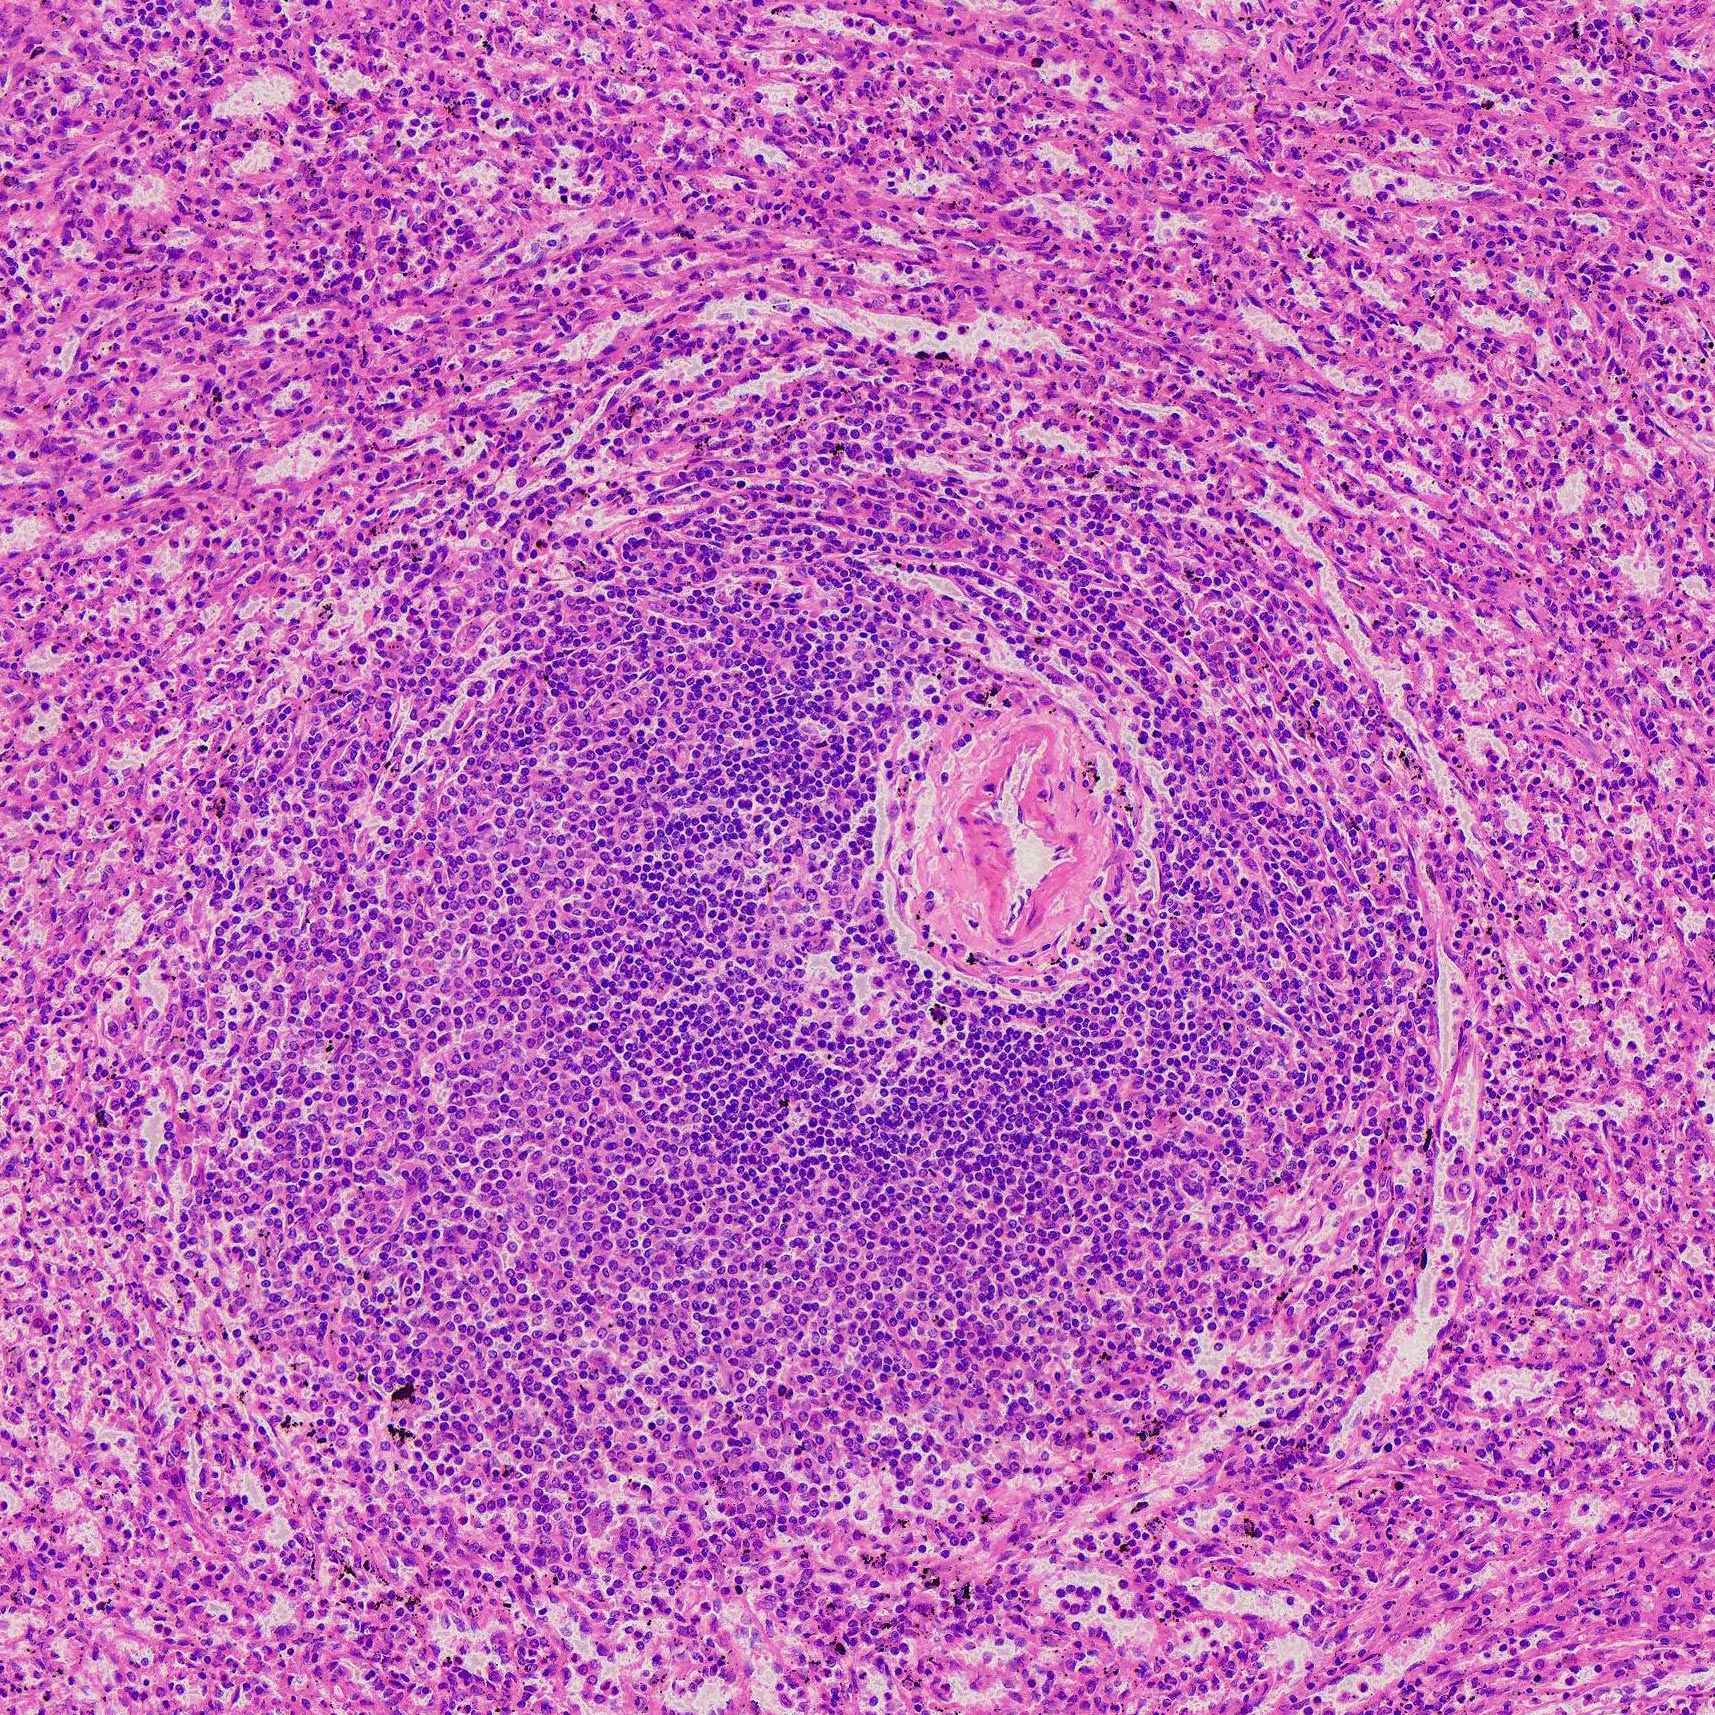

Thickness: 7-micrometer section

Stain: hematoxylin and eosin

Description of the Human spleen section:

- Thickness: 7-micrometer section

- Stain: hematoxylin and eosin

- Show: red pulp, splenic nodule, central artery